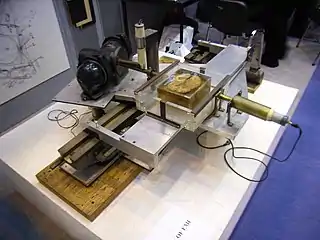

En los fundamentos de esta técnica trabajaron de forma independiente el físico y cristalógrafo sudafricano nacionalizado estadounidense Allan MacLeod Cormack y el ingeniero electrónico inglés Sir Godfrey Newbold Hounsfield, que dirigía la sección médica del Laboratorio Central de Investigación de la compañía EMI. Ambos obtuvieron de forma compartida el Premio Nobel de Fisiología o Medicina, en 1979.

En 1967, Cormack publica sus trabajos sobre la TC siendo el punto de partida de los trabajos de Hounsfield, que diseña su primera unidad. En 1972 comenzaron los ensayos clínicos cuyos resultados sorprendieron a la comunidad médica, si bien la primera imagen craneal se obtuvo un año antes.

Los primeros cinco aparatos se instalaron en Reino Unido y los Estados Unidos; la primera TC de un cuerpo entero se consiguió en 1974.

Para aplicarlo a la medicina hubo que esperar al desarrollo de la computación y del equipo adecuado que mezclase la capacidad de obtener múltiples imágenes axiales separadas por pequeñas distancias, almacenar electrónicamente los resultados y tratarlos. Todo esto lo hizo posible el británico G. H. Hounsfield en la década de 1970.